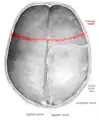

![]() Superior view of the skull. ("Coronal suture" in red.) | |

The coronal suture lies between the paired parietal bones and the frontal bone of the skull.[1] It runs from the pterion on each side.

Superior view of anterior part of the skull. Coronal suture runs horizontally.